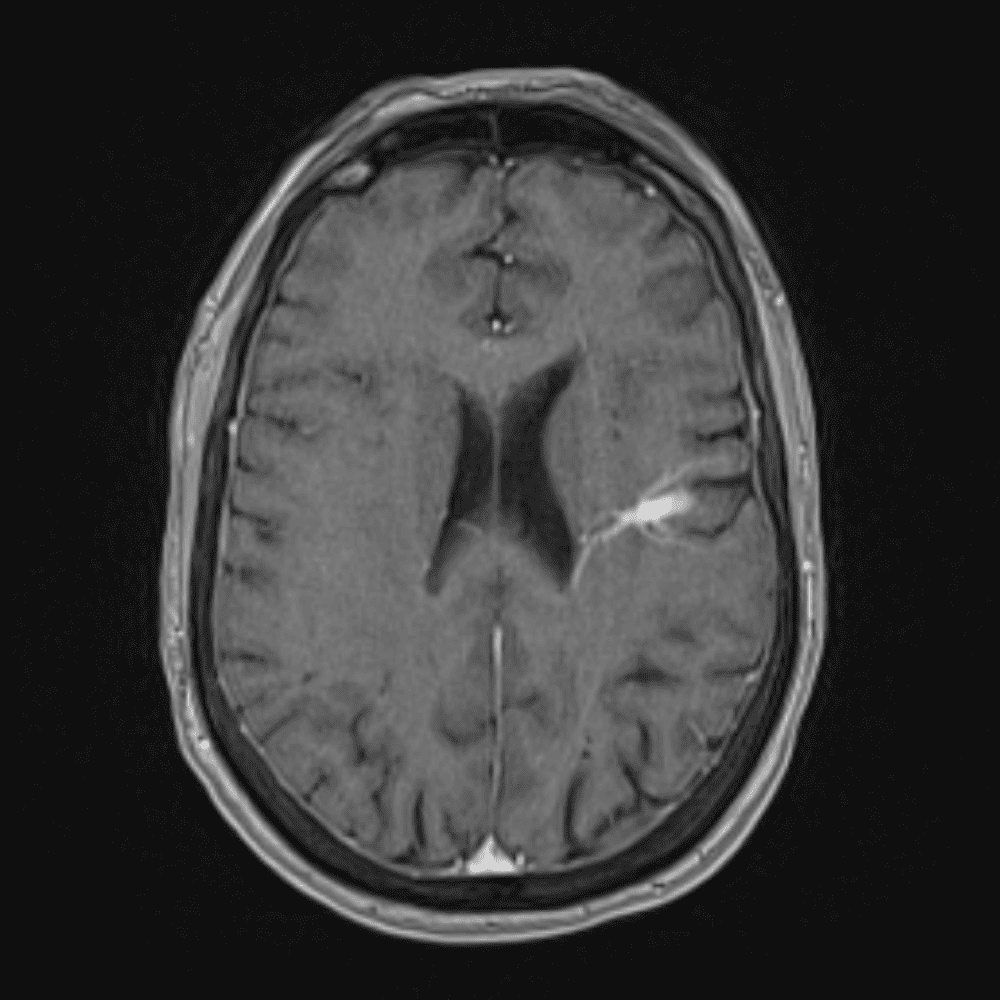

๋‹น์ง ์‹œ ํ”ํžˆ ๋ณผ ์ˆ˜ ์žˆ๋Š” ์‚ฌ๋ก€์˜ ์ „ํ˜•์ ์ธ ์˜ˆ๋ฅผ ํฌํ•จํ•ฉ๋‹ˆ๋‹ค.

39 ์‚ฌ๋ก€

์—ฐ์Šต

๋ฏธ๋ฌ˜ํ•˜๊ฑฐ๋‚˜ ์–ด๋ ค์šด ์‚ฌ๋ก€์™€ ์ผ๋ถ€ ์ •์ƒ ์‚ฌ๋ก€๋ฅผ ํฌํ•จํ•˜์—ฌ ๋‹น์ง์„ ์‹œ๋ฎฌ๋ ˆ์ด์…˜ํ•ฉ๋‹ˆ๋‹ค.

50 ์‚ฌ๋ก€